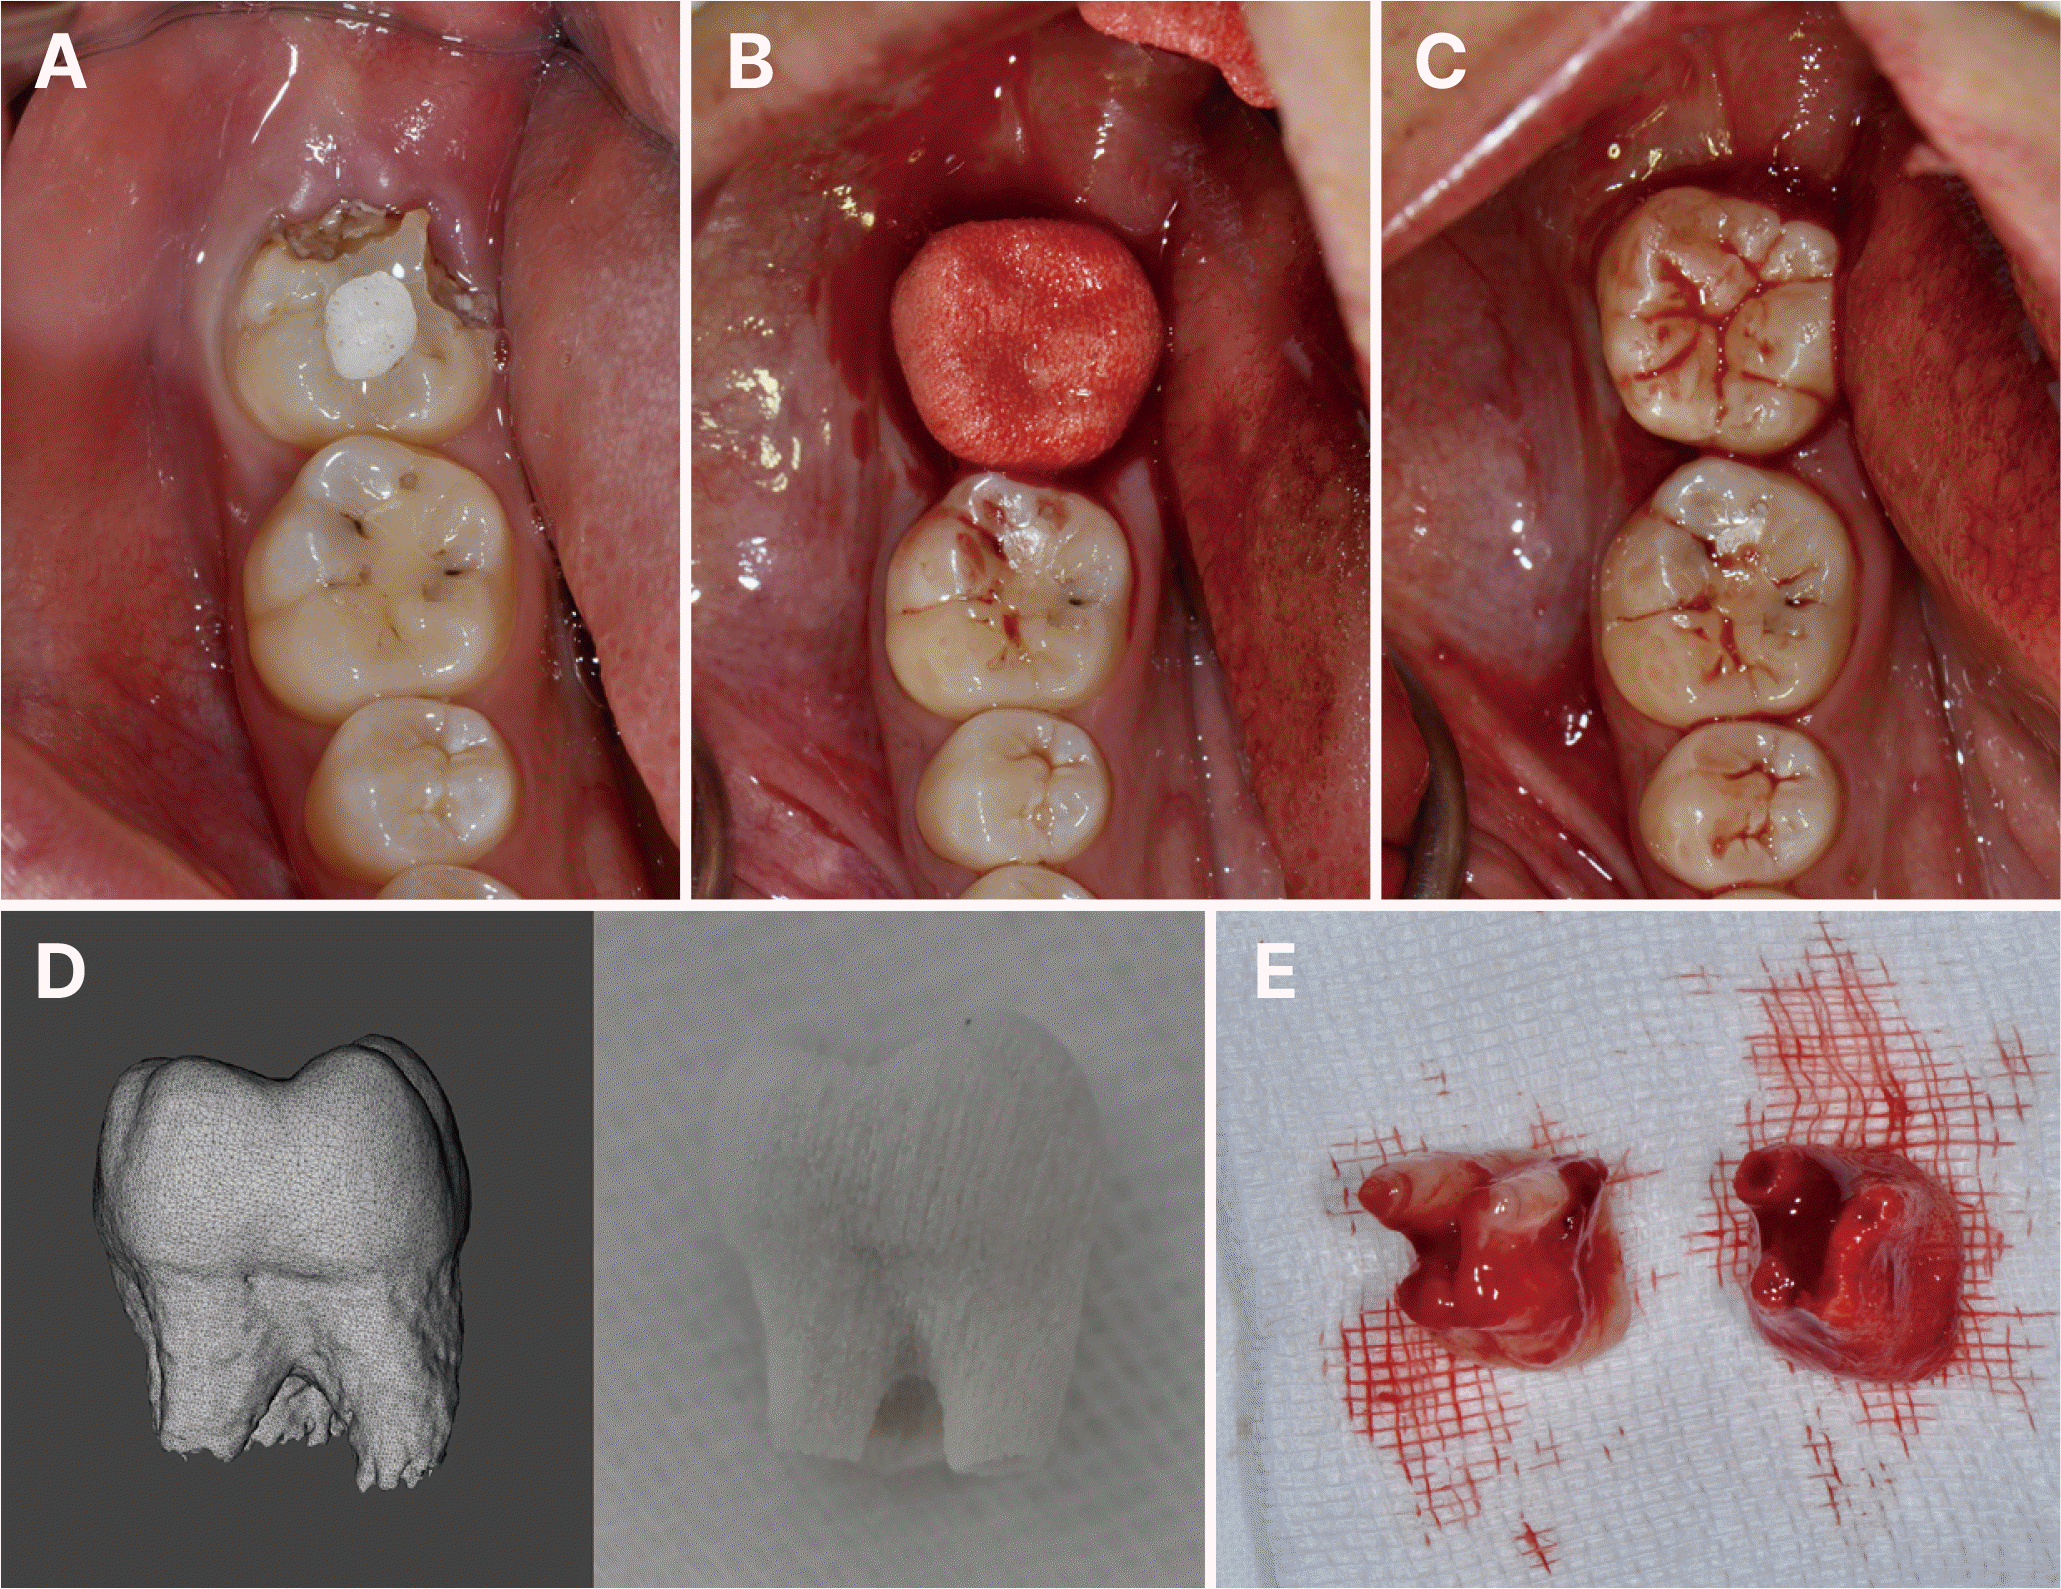

술 전 동의서를 받은 후, 국소마취 하에서 자가치아이식 수술을 시행하였다. 기존 하악 우측 제2대구치를 발치한 후, 수여부에 CARP model을 적합시켜 확인하였고(Fig. 2A, 2B), 이를 바탕으로 수여부를 형성하였다. 상악 우측 제3대구치를 최소한의 외상으로 조심스럽게 발치한 후 수여부에 이식하였으며(Fig. 2C), 발치된 공여치와 CARP model의 정확한 일치를 확인할 수 있었다(Fig. 2D). 교합 조정 후 치아의 안정성을 위해 인접치와 레진 강선(Resin-wire splint)으로 고정하였다. 전체 술식에서 공여치의 구강 외 시간은 3분 이내로 제한하였다.

수술 10일 후 임상검사에서 정상적인 초기 치유 양상이 관찰되어 강선고정은 제거하였다(Fig. 3A - 3C). 이후 1.5개월 시점의 추적 관찰에서도 양호한 치유 상태가 확인되었다(Fig. 3D). 이후 3개월, 6개월, 1년 간격으로 정기검진을 시행하였다. 술 후 3개월째 임상검사에서 3 mm 이내의 치주낭 깊이와 정상적인 동요도를 보였으며, 냉검사에 양성 반응을 나타내어 치수 생활력이 회복되었음을 확인할 수 있었다. 수술 2년 4개월 시점의 방사선 사진에서 완전한 치근 형성이 확인되었다(Fig. 4A - 4C). 수술 뒤 3년 10개월 시점이 이식치아의 후방 제3대구치가 맹출하여 환자에게 하악 우측 제3대구치의 발치를 권고하였다(Fig. 4D - 4F).

Fig. 2

Computer-aided rapid prototyping (CARP) guided autotransplantation procedure. (A) Pre-operative clinical photographs showing status of recipient site. (B) CARP model in recipient site. (C) Donor tooth in recipient site. (D) 3D-rendered donor tooth and CARP model comparison. (E) Extracted donor tooth and CARP model comparison.

Fig. 3

Post-operative follow-up images. (A) Panoramic radiograph at 10 days after surgery. (B) Periapical radiograph at 10 days after surgery. (C) Clinical photograph at 10 days after surgery. (D) Clinical photograph at 1.5 months after surgery.